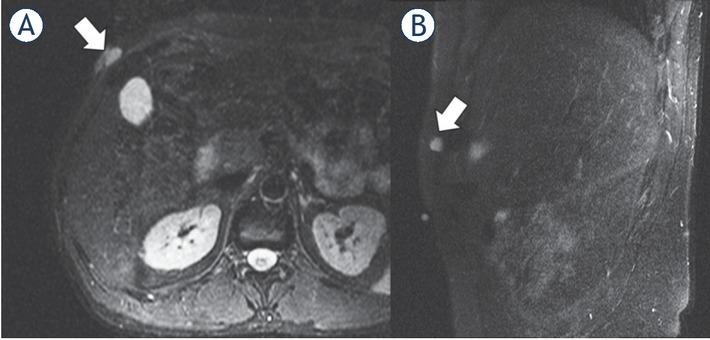

Figure 4

1.5-T MRI of the pelvis

![1.5-T MRI of the pelvis (A) proton density [PD] fat saturation [FS]: coronal, (B) PD FS axial, (C) contrast-enhanced T1 FS axial) of a 51-year-old patient. The low-grade sarcoma in the right gluteal region (white arrow) shows an ovoid/nodular configuration and well-defined borders.](https://sciendo-parsed-data-feed.s3.eu-central-1.amazonaws.com/60724a50989a071a6405e20e/j_raon-2021-0007_fig_004.jpg?X-Amz-Algorithm=AWS4-HMAC-SHA256&X-Amz-Date=20220819T130336Z&X-Amz-SignedHeaders=host&X-Amz-Expires=18000&X-Amz-Credential=AKIA6AP2G7AKP25APDM2%2F20220819%2Feu-central-1%2Fs3%2Faws4_request&X-Amz-Signature=7e8b190dda69351ad5e27ba52ed7950527fd77ee1e59373c2ea33329b93f8d86)